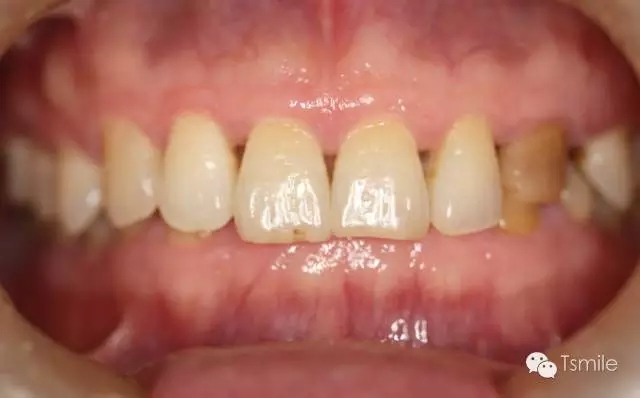

圖2: 前牙功能范圍受限導(dǎo)致的前牙重度磨耗

磨耗患者中還有一類特殊的局限于上下前牙區(qū)的牙齒重度磨耗,表現(xiàn)為上前牙舌面、下前牙切端和唇面的重度磨耗。該類患者常表現(xiàn)為一類特殊的咬合類型,重度深覆頜或者上前牙明顯舌傾,這種咬合類型導(dǎo)致下頜前伸功能運(yùn)動(dòng)受限,從而導(dǎo)致前牙區(qū)重度的磨耗,可稱為前牙功能范圍受限(restricted envelope of function)。